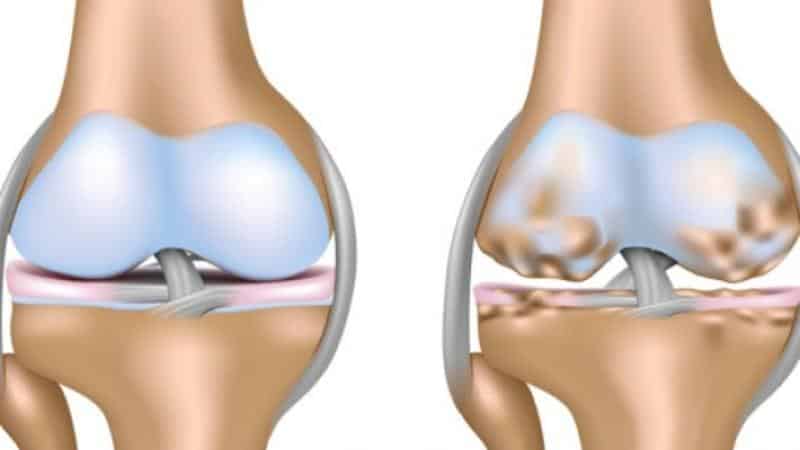

Начало патологического процесса выражено минимальными поражениями гиалиновых хрящей, что в результате приводит к последующим переменам в сопутствующих тканях. Начинает развиваться хронический процесс поражения синовиальных суставов.

Остеоартроз. Дефект суставного хреща